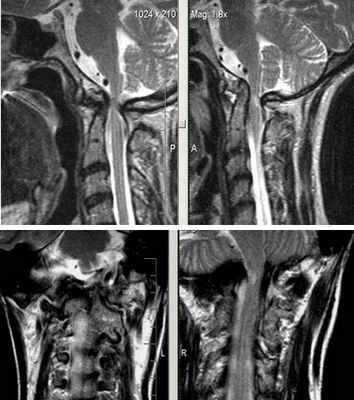

МРТ исследование краниовертебрального перехода

Аномалия кранио-вертебрального перехода: ассимиляция С1, затылочной кости, зубовидного отростка С2 позвонка; базиллярная импрессия. Ротационное смещение С1 позвонка, гипертрофия боковых масс тела С1 позвонка. Стеноз большого затылочного отверстия. Очаговая миелопатия на уровне С2 позвонка.

Сращение правых отделов боковых масс атланта и основания затылочной кости (синостоз правого атланто-окципитального сочленения).